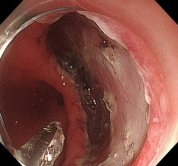

早期食管癌及内镜手术

消化道早癌的病例展示(经内镜手术或活检证实):

十二指肠降段早癌

十二指肠溃疡降段早癌的内镜粘膜剥离手术治疗(ESD)